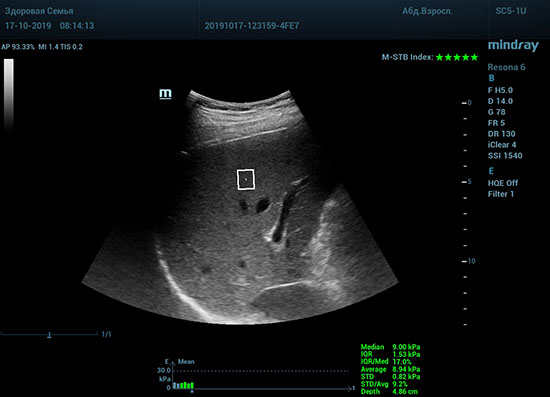

Определение плотности печени. Не ошибся ли оператор при измерении эластических свойств печени? Для оценки критериев качества предусмотрен индекс MBT, который покажет насколько «твердой» была рука оператора и двигалась ли печень. При MBT 5* рука тверда и показатели достоверны. Для оценки качества результатов используется IQR индекс, отображающий колебания показателей в точке измерения при расчете медианы. Показатели при IQR <30% считаются приемлемыми. Техника сканирования через межреберные промежутки требует размещение окна интереса на несколько сантиметром ниже капсулы, для исключения эффекта реверберации. Установка ROI на паренхиму без захвата сосудов, для исключения погрешностей измерения.

Стадия фиброза определяется по системе METAVIR Staging, построенной на данных биопсии и сопоставлении с данными эластографии. Своевременная диагностика фиброза, и начало его лечения, залог благоприятного исхода заболевания.